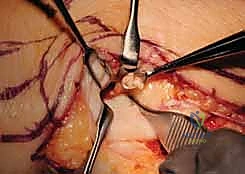

The Ulnar Osteotomies

"Alright, the ulna is well exposed. Let's bring in the C-arm to confirm our osteotomy sites." We must execute two precise cuts to create the pseudoarthrosis gap.

- The Distal Cut: We plan the first cut just proximal to the metaphyseal flare of the ulnar head. We must ensure we are entirely proximal to the articular surface of the DRUJ, yet distal enough to leave a robust block of bone that can accommodate two 3.5 mm or 4.0 mm screws. We verify this level with fluoroscopy. Using a small oscillating microsaw with a fresh blade, we make a clean, perpendicular cut across the ulnar shaft. Copious, continuous saline irrigation is applied directly to the blade to prevent thermal necrosis of the bone, which could compromise our arthrodesis.

Clinical & Radiographic Imaging Archive